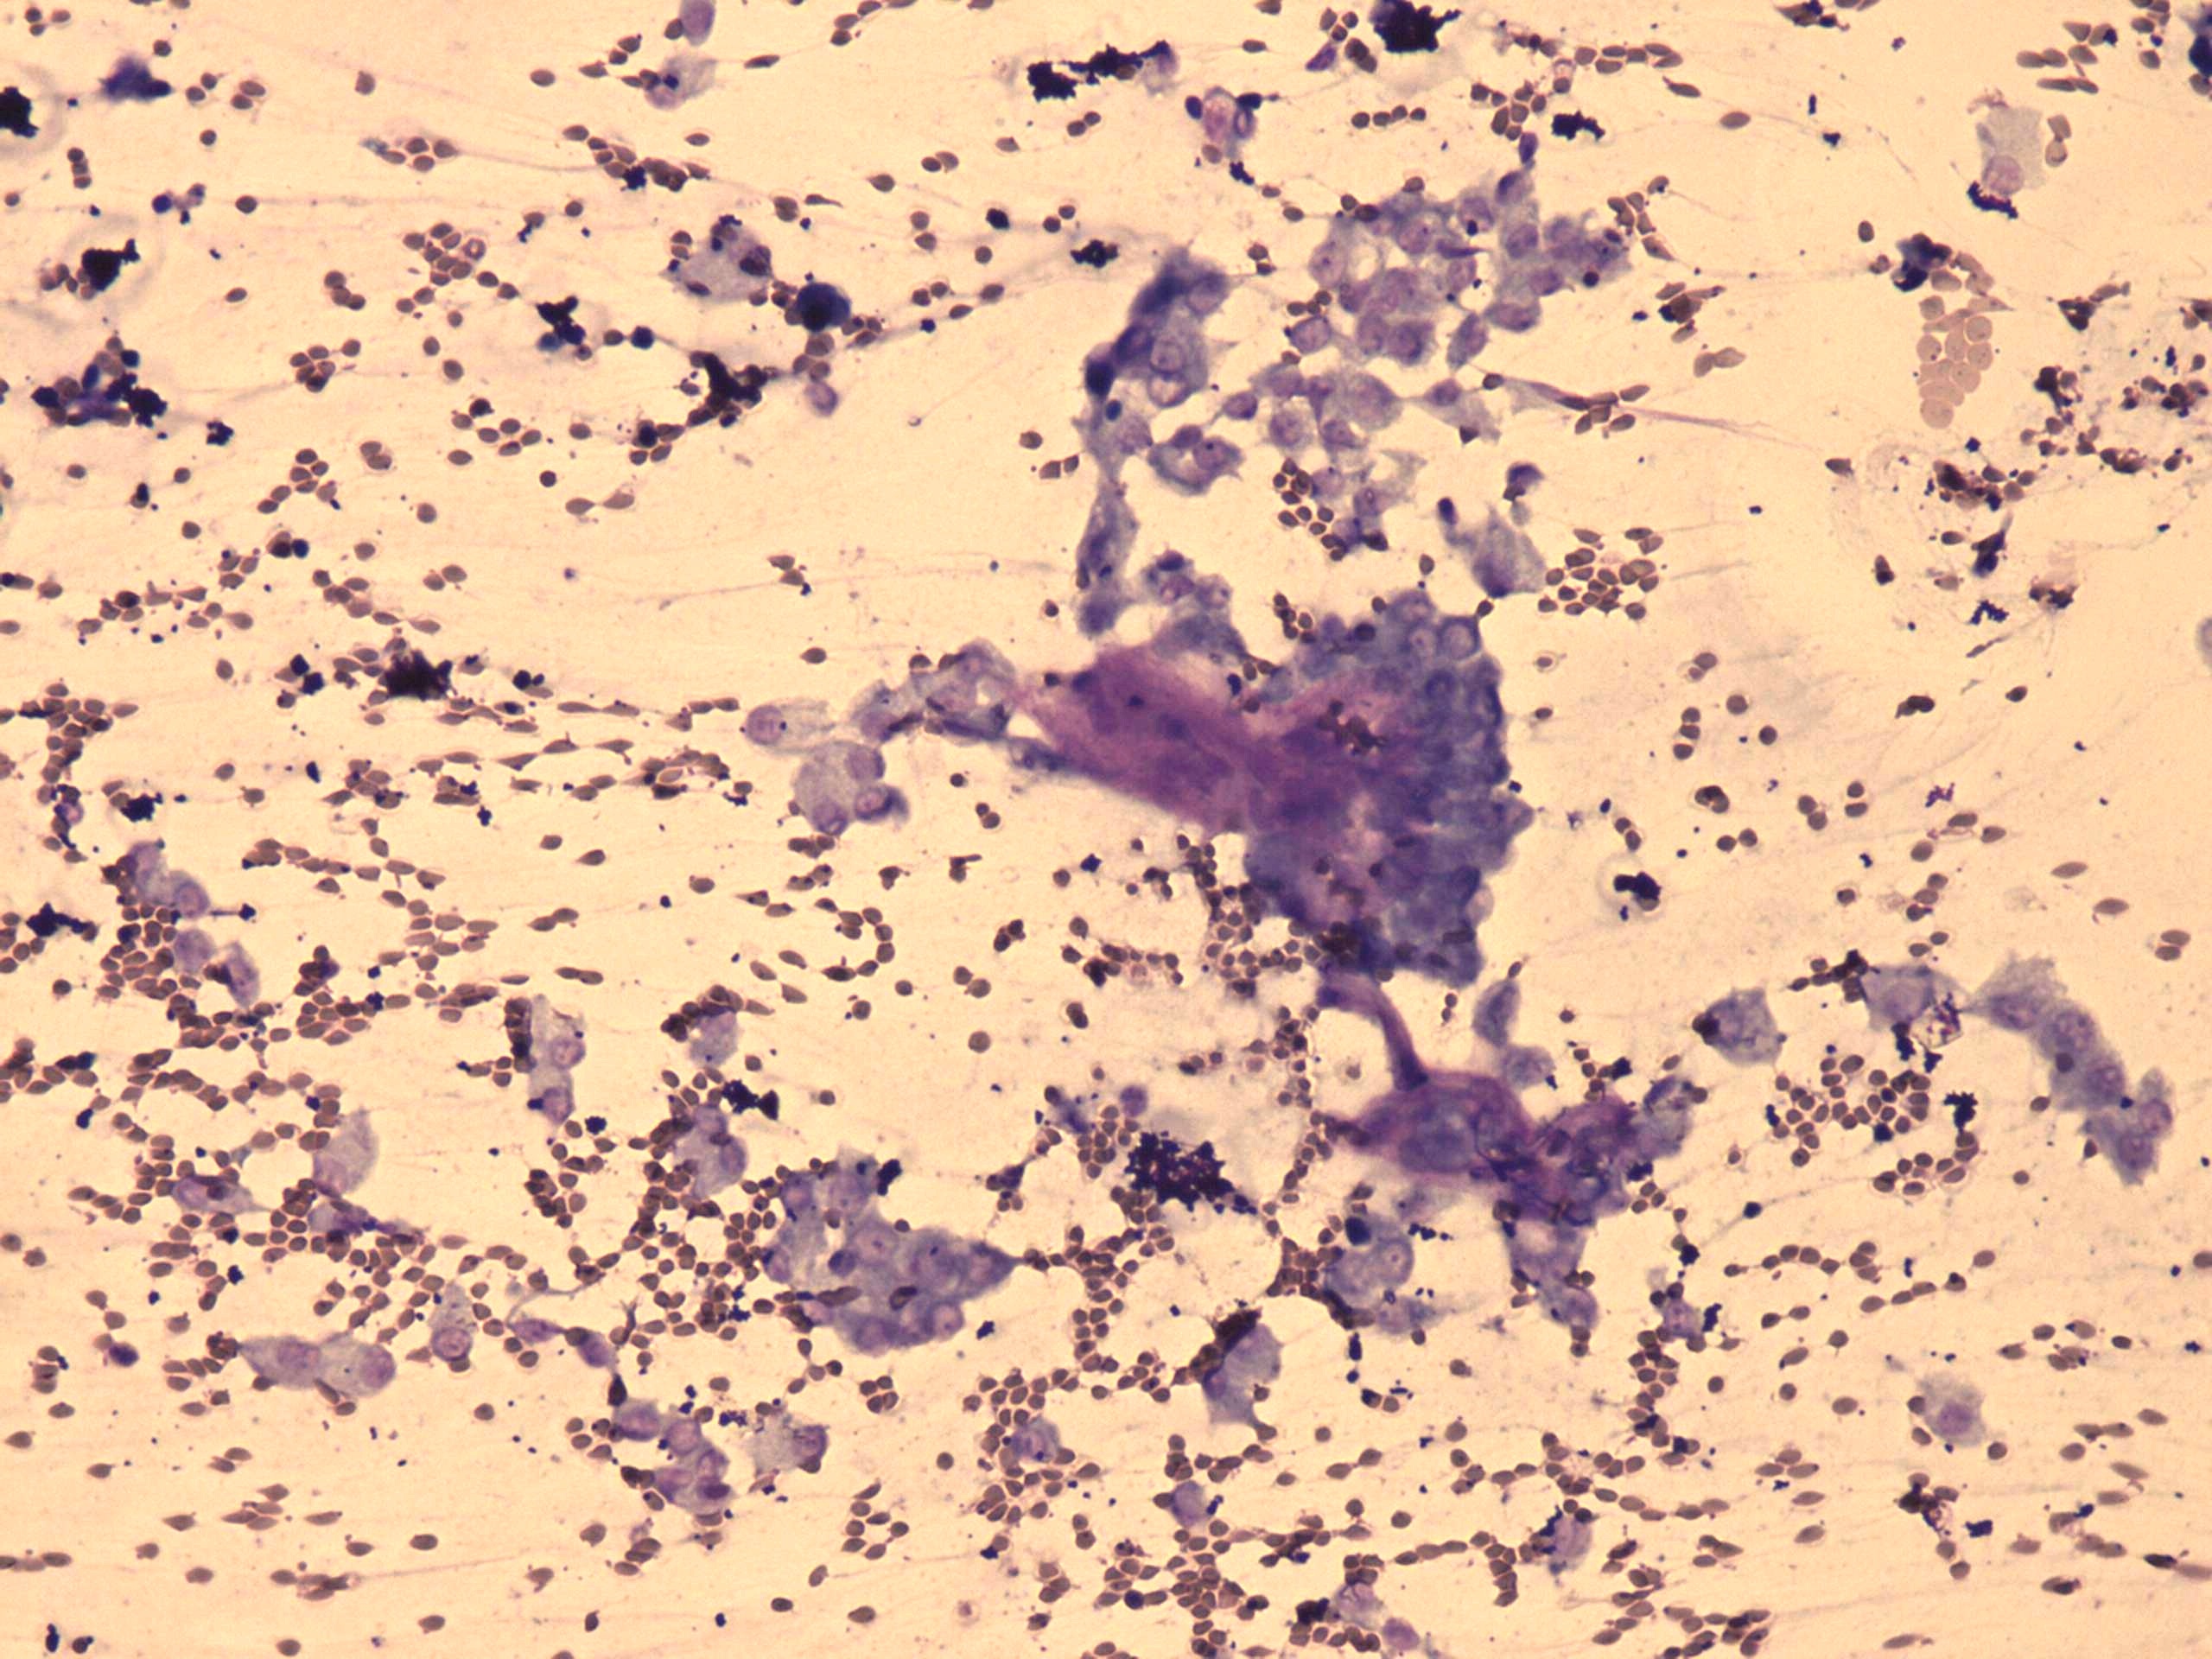

Wright-Giemsa staining, 200x.   The nuclei are vesicular and have inconspicious nucleoli.